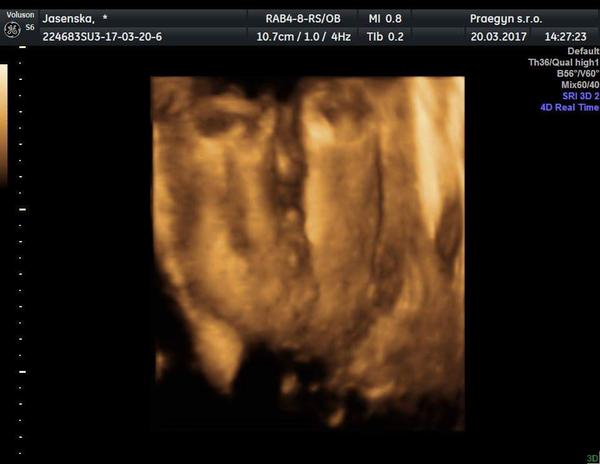

Tak ja hlasim,ze cekame chlapecka.. Uz je to 100% podle 3D na ktery jsem sla hlavne kvuli pohlavi....18 a 21 tt mi MUDr. Tvrdil holku... 23tt velky utz jina MUDr. Rekla kluk- viz moje fotka,kterou jsem zde dala v unoru.. A pak 25 tt pro zmenu neslo nic moc videt.. a konecne o 10 dni pozdeji na 3D je tato fotka. A ja zacinam nakupovat klucici veci a zvykam si definitivne na to,ze budu doma jedina zenska :D .. A zajimalo by me,jak je na tom @wond3r?

@andy11111 tipla bych to na holčičku, mám doma podobný obrázek a už vím určitě, že to bude holčička 🙂

@tomikjoejoe Vypada to tak,ale porad si davam nejakou nadeji,ze by ten pinda mohl byt jeste schovany🙂 Ale,kdyz to bude holka,tak ji budu mit stejne rada jako kluka;)

@mariejosef To urcite,jsem za ni rada.Jen jestli se treba nekomu nestalo,ze se z tohodle objevil jeste pinda🙂